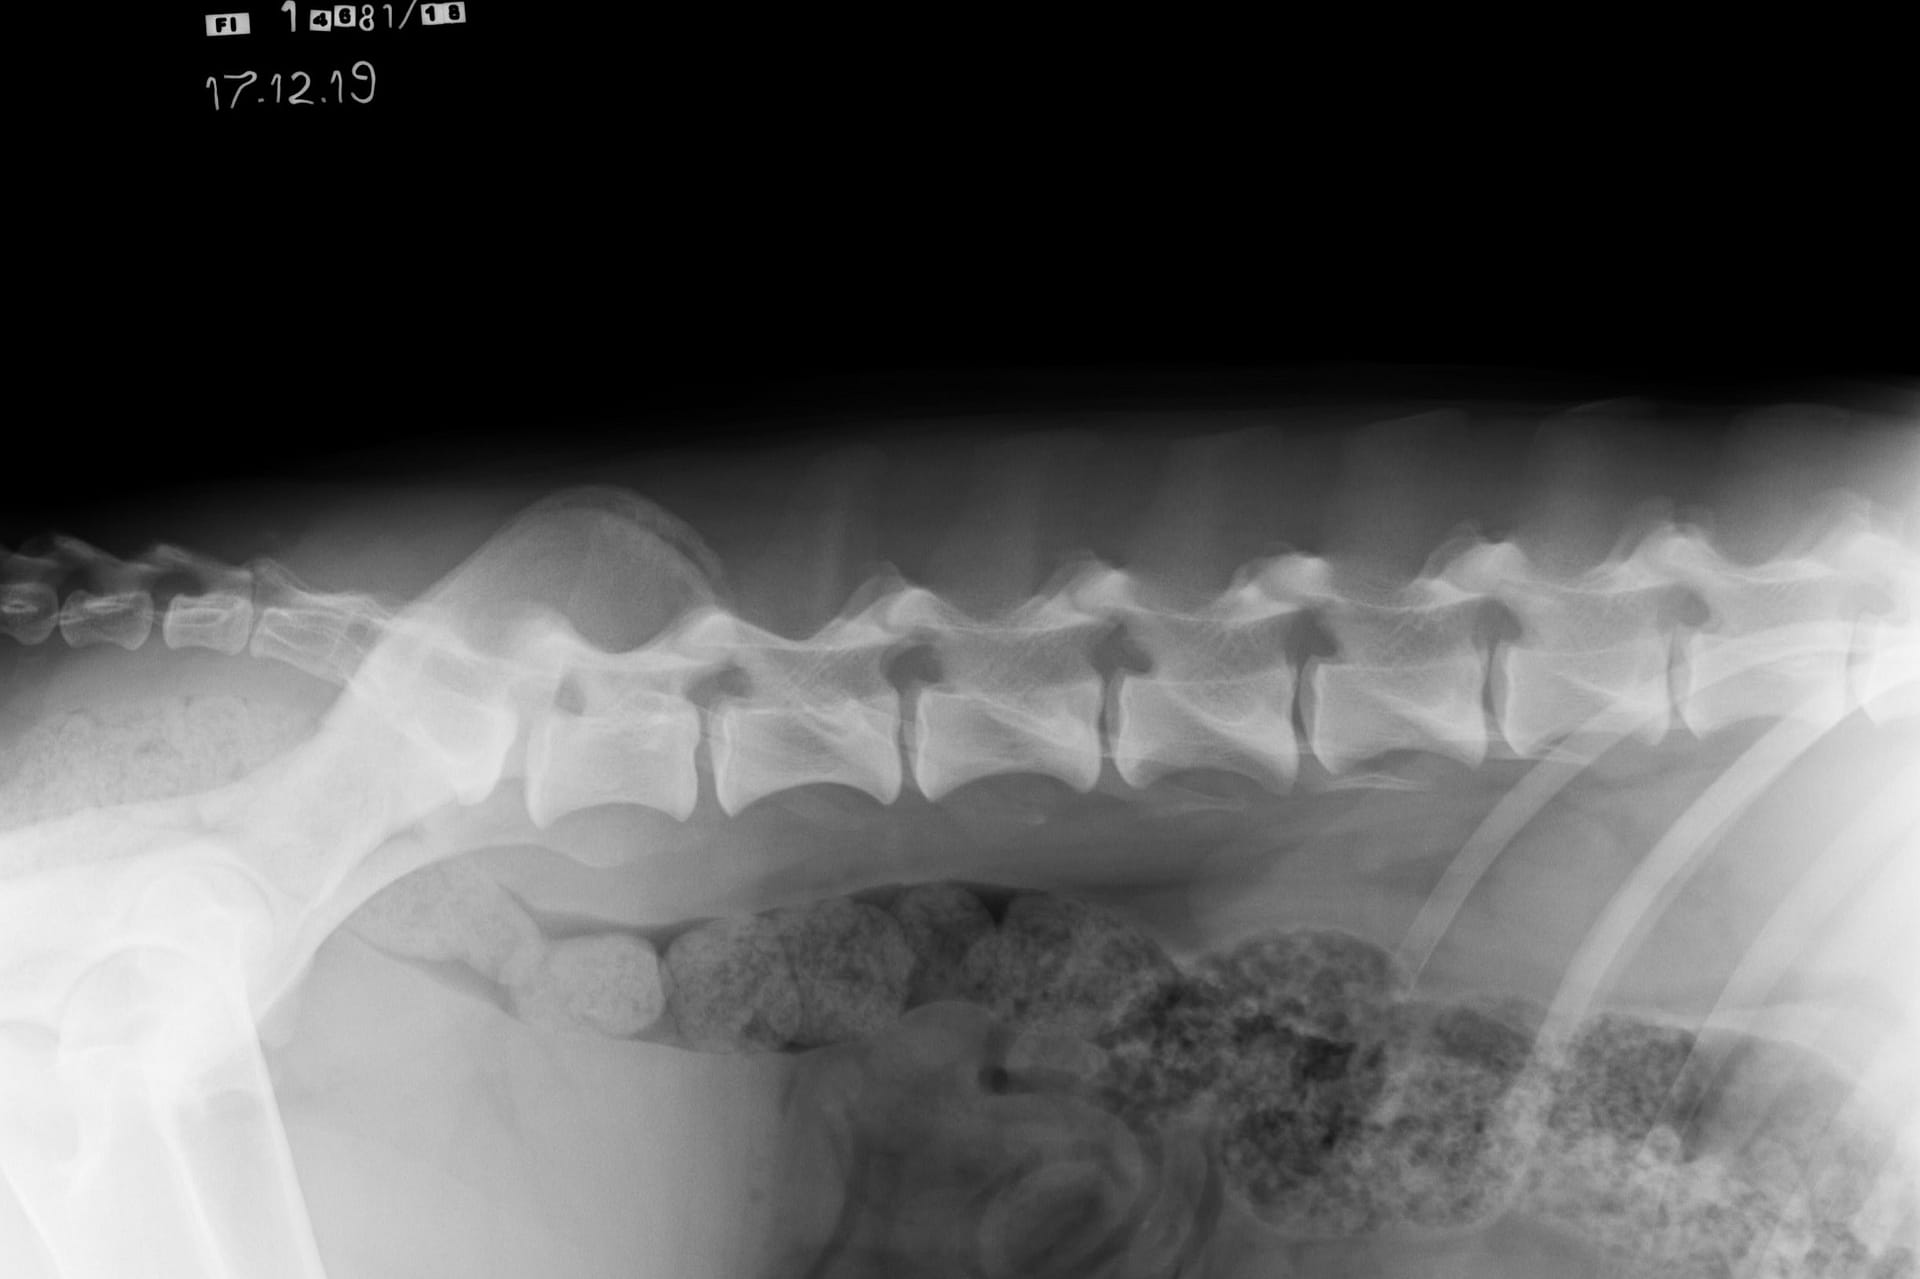

Kuvaamalla kaula-, rinta- ja lannerangan sekä ristiluun voi saada selkälausunnon LTV:stä, spondyloosista ja epämutoisista nikamista (VA). LTV- ja VA-lausunnon saa 12 kk ikäiselle koiralle ja spondyloosilausunnon 24 kk ikäiselle. Kennelliiton ohje selkärangan kuvaamiseen: https://www.kennelliitto.fi/lomakkeet/selkarangan-kuvauksen-suoritus

NORMAALI SELKÄRANKA

Koiran normaali selkäranka koostuu seitsemästä kaulanikamasta (C1-7), kolmestatoista rintanikamasta (T1-13), seitsemästä lannenikamasta (L1-7) ja kolmesta ristinikamasta (S1-3). Nikamien laskenta aloitetaan ensimmäisestä rintanikamasta (T1). Häntänikamien CD) määrä vaihtelee.